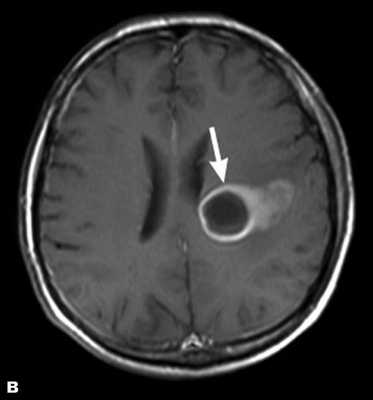

Злокачественные опухоли характеризуются инвазивностью, то есть врастанием в здоровые ткани, поэтому контуры таких образований нечеткие и неровные, а потому достоверно определять границы таких опухолей довольно сложно. Кроме того, структура злокачественной опухоли часто бывает неоднородна за счет распада (некроза), кровоизлияния и коллоидной дегенерации. Вокруг злокачественной опухоли, как правило, выявляется выраженный перифокальный отек, который может приводить к смещению срединных структур головного мозга и появлению аксиальной дислокации. Также могут быть выявлены признаки метастазирования.

При МРТ головного мозга в левом мосто-мозжечковом углу определялось больших размеров округлой формы внемозговое патологическое образование, с четкими ровными контурами, широким основанием, прилежащее к твердой мозговой оболочке. После внутривенного контрастирования отмечалось равномерное, выраженное усиление интенсивности МР-сигнала от вышеописанного образования, а также твердой мозговой оболочки. Пациенту был поставлен диагноз (менингиома левого мосто-мозжечкового угла).